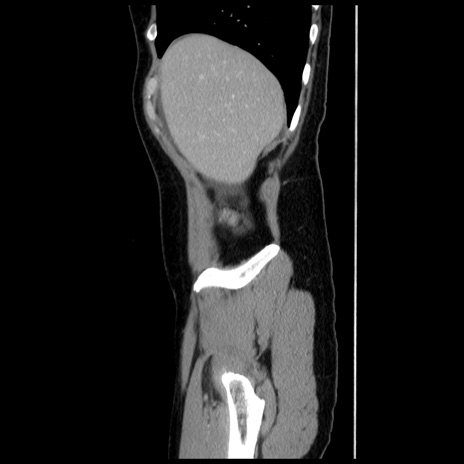

症例10(矢状断像)

【症例】 50歳代女性

【主訴】 腹痛

【現病歴】前日生レバーを食べた。今朝に排便あり。 昼前に突然発症の腹痛を生じ、当院救急外来を受診した。

【既往歴】 子宮筋腫にてで子宮全摘後

【身体所見】 意識清明、腹部:平坦、軟、下腹部やや左を中心に圧痛・反跳痛あり、筋性防御あり

【データ】WBC 7800、CRP 0.07